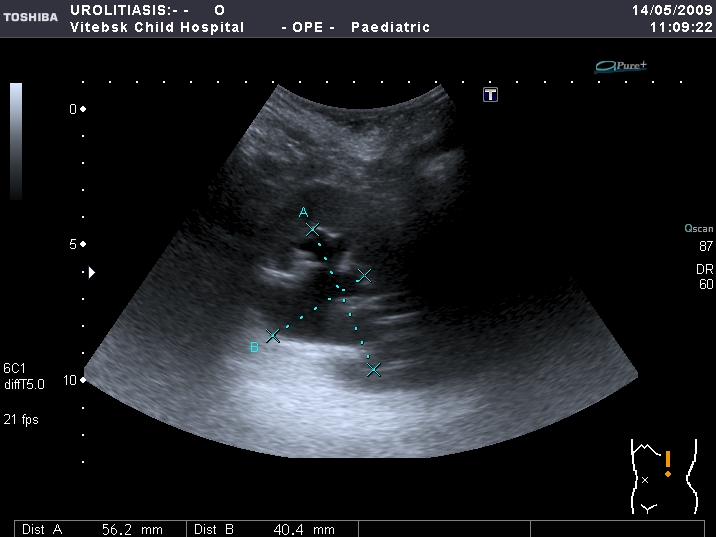

Мочеточники в нижней трети

Нейрогенный мочевой пузырь (?), МКБ, конкремент мочевого пузыря, двухсторонний мегауретер, конкремент правой почки.

Возможно, в дивертикуле либо в нижней трети мочеточника..